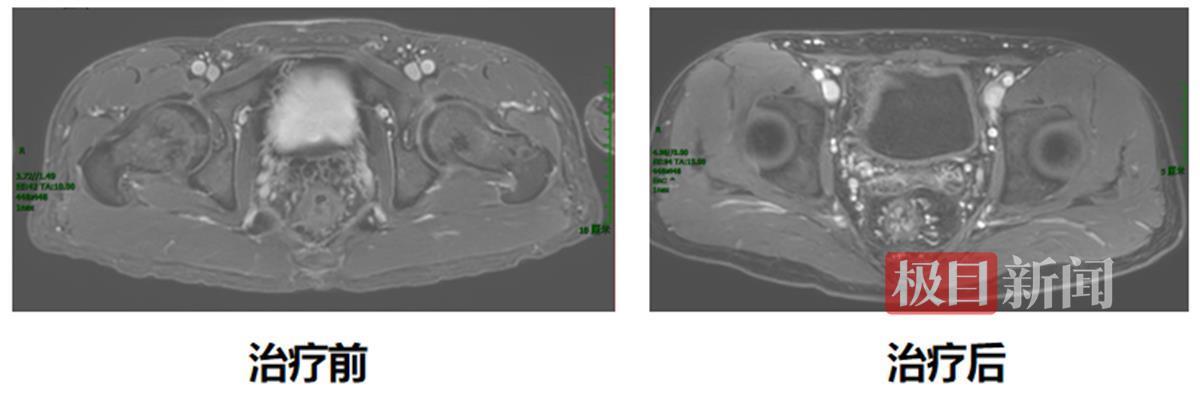

今年33岁的小江(化名)是接受该创新治疗模式的患者之一。2023年9月,他因便血1年多,最近一个多月又出现肛门坠胀在外院就诊,腹部CT检查提示直肠下段肿瘤性病变,经活检证实为腺癌。医院建议进行手术治疗,但小江保肛意愿强烈,为寻求进一步治疗,于是来到协和医院就诊。入院后,经过磁共振检查及病理会诊,他被确诊为低位直肠腺癌T3N2M0,肿瘤下缘距离肛门口仅2厘米,保肛难度非常大。

经过胃肠外科、腹部肿瘤科、影像科、病理科等多学科讨论后,最终决定采用新疗法。2023年9月,小江接受了5次直肠病灶及淋巴结引流区放疗,随后进行化疗联合免疫新辅助治疗,今年1月再次复查肠镜发现,他的直肠下段肿瘤病灶已经消失,获得了临床完全缓解。这也意味着小江的肿瘤术前完全消退,后续接受规范的监测和复查即可。